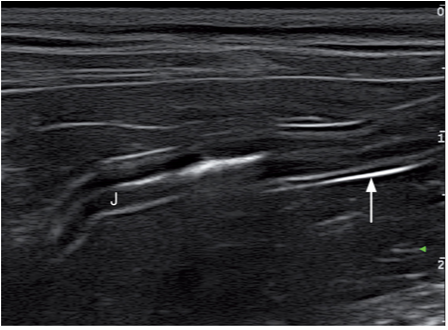

腹膜壁层在近场上呈现一条高回声亮线(图1)。器官表面的腹壁脏层又称为浆膜层,包裹在肠道外壁,胃的外壁,膀胱的外壁,脾脏和肝脏的外壁,也呈高回声的亮线(图2)。腹膜结缔组织连接腹腔各个器官,有3个双层腹膜结构,分布是网膜,肠系膜,韧带(图3)猫的镰状韧带位于肝的腹侧被脂肪组织所包裹,相较于肝脏实质的回声镰状韧带可呈无回声或低回声,偶尔呈高回声,它的质地更加粗糙些(图4)。肝脏包膜的高回声亮线是镰状韧带和肝脏实质的分界。而猫的分界线比较模糊,没有经验医生很难将镰状韧带和肝脏实质区分开。可能会将镰状韧带误认为是肝脏,在进行细针抽吸时吸出的不是肝脏组织而是脂肪。